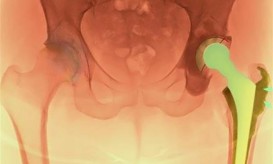

Οι νεότερες τεχνολογίες και χειρουργικές τεχνικές που αφορούν στην αρθροπλαστική του ισχίου και του γόνατος παρουσιάζονται στο διήμερο ευρωπαϊκό...

Οι νεότερες εξελίξεις στην Αρθροπλαστική Ισχίου και Γόνατος θα αναπτυχθούν στο Συνέδριο “What is new in Hip & Knee...